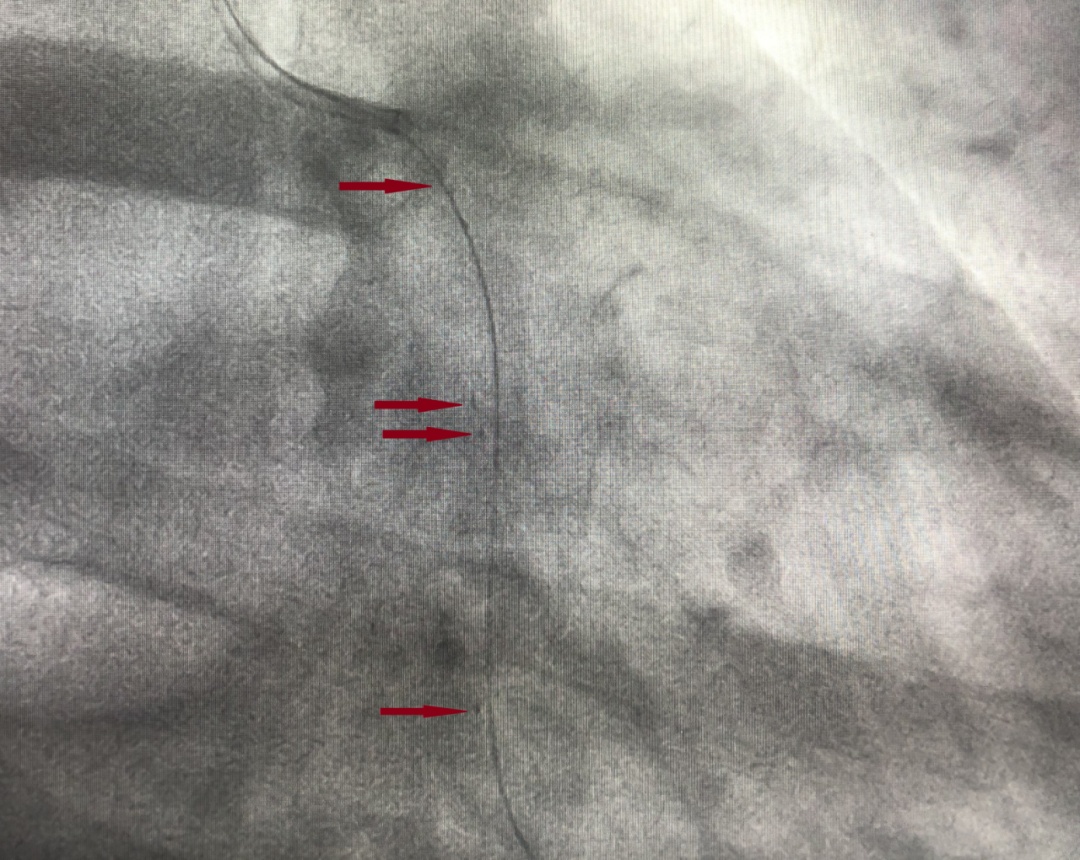

红色箭头处可见BRS两侧的铂金Marker;串联(头尾相连但无重叠)植入2枚支架

可吸收支架